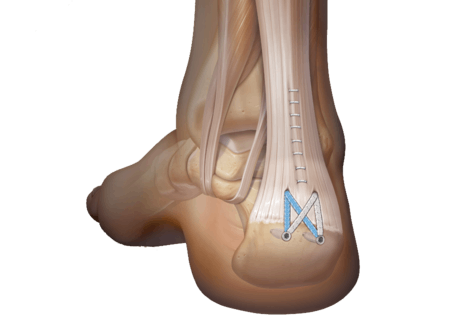

A cirurgia é sempre necessária para tratar a tendinite de Aquiles?

De jeito nenhum! A cirurgia é reservada para casos mais graves e que não responderam ao tratamento conservador. Na maioria das vezes, com fisioterapia e repouso, você se recupera bem.